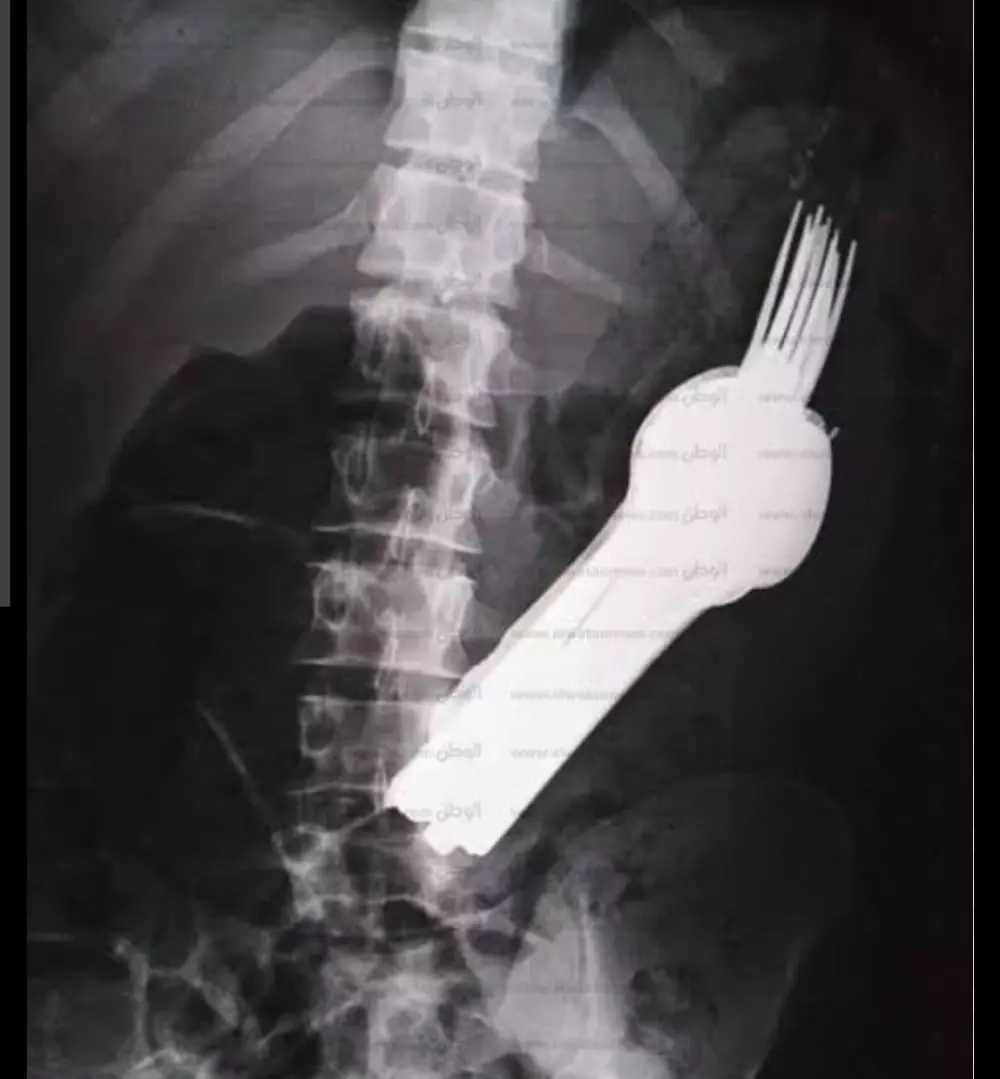

اقدم لك دوره تدريبيه من خلالها يمكنك قراءة أشهر 25 تحليل وتقارير جميع انواع الأشعه مع التطبيق عمليا من خلال إحضار تقارير ونتدارسها سويا وذلك لاطمئنانك فقط قبل الذهاب للطبيب المختص أو للعلم إن كنت من طلاب المجال الطبي الدوره متاحه للجميع لا يشترط أن تكون من طلاب المجال الطبي فقط فهي للعلم والمعرفه وليست للتشخيص والعلاج من خلال هذه الدور سوف تتعلم 1.أسماء التحاليل ومتى تطلب من المريض 2.النسب الطبيعيه للعناصر والمواد الكيميائيه الموجوده في الجسم 3.سبب ارتفاع أو انخفاض هذه النسب وما المترتب على ذلك 4.ستعرف أيضا مما يعاني صاحب التحليل أو الأشعه 5. أعلمك كيف تقرأ تقرير الأشعه باستفاضة ومعرفة نتيجته 6.اعلمك الفرق بين انواع الاشعه مثل الأشعه المقطعيه والرئتين المغناطيس والأشعه بالصبغة والأشعه التداخليه والأشعه السينية والمسح الذري ومتى تطلب كل واحده 7.اعلمك قراءة الفيلم الموجود مع التقرير وكيف تظهر الدهون في الاشعه والعظام المكسوره وكيف تظهر الدهون وجميع أنسجة الجسم في الفيلم (الفيلم هو الورقه السوداء) الموجوده مع التقرير 8.كيف تظهر الأورام والجلطات في الأشعه مدة الدوره 3 ايام بمقدار ساعتين يوميا عبر موقع زوم أو تيشمنت بالإضافه إلى شهادة حضور موثقه في نهاية الدوره أول يومين للتدريب والتعرف على تقارير التحاليل اليوم الثالث للأشعه سعر الدوره كامله شامله ال3 ايام وشهادة الحضور 30 دولار فقط إن لم تستفيد من الدوره يمكنك استرداد المبلغ واطمأن لن تسترده لأنك حتما ستستفيد 100% والسلام